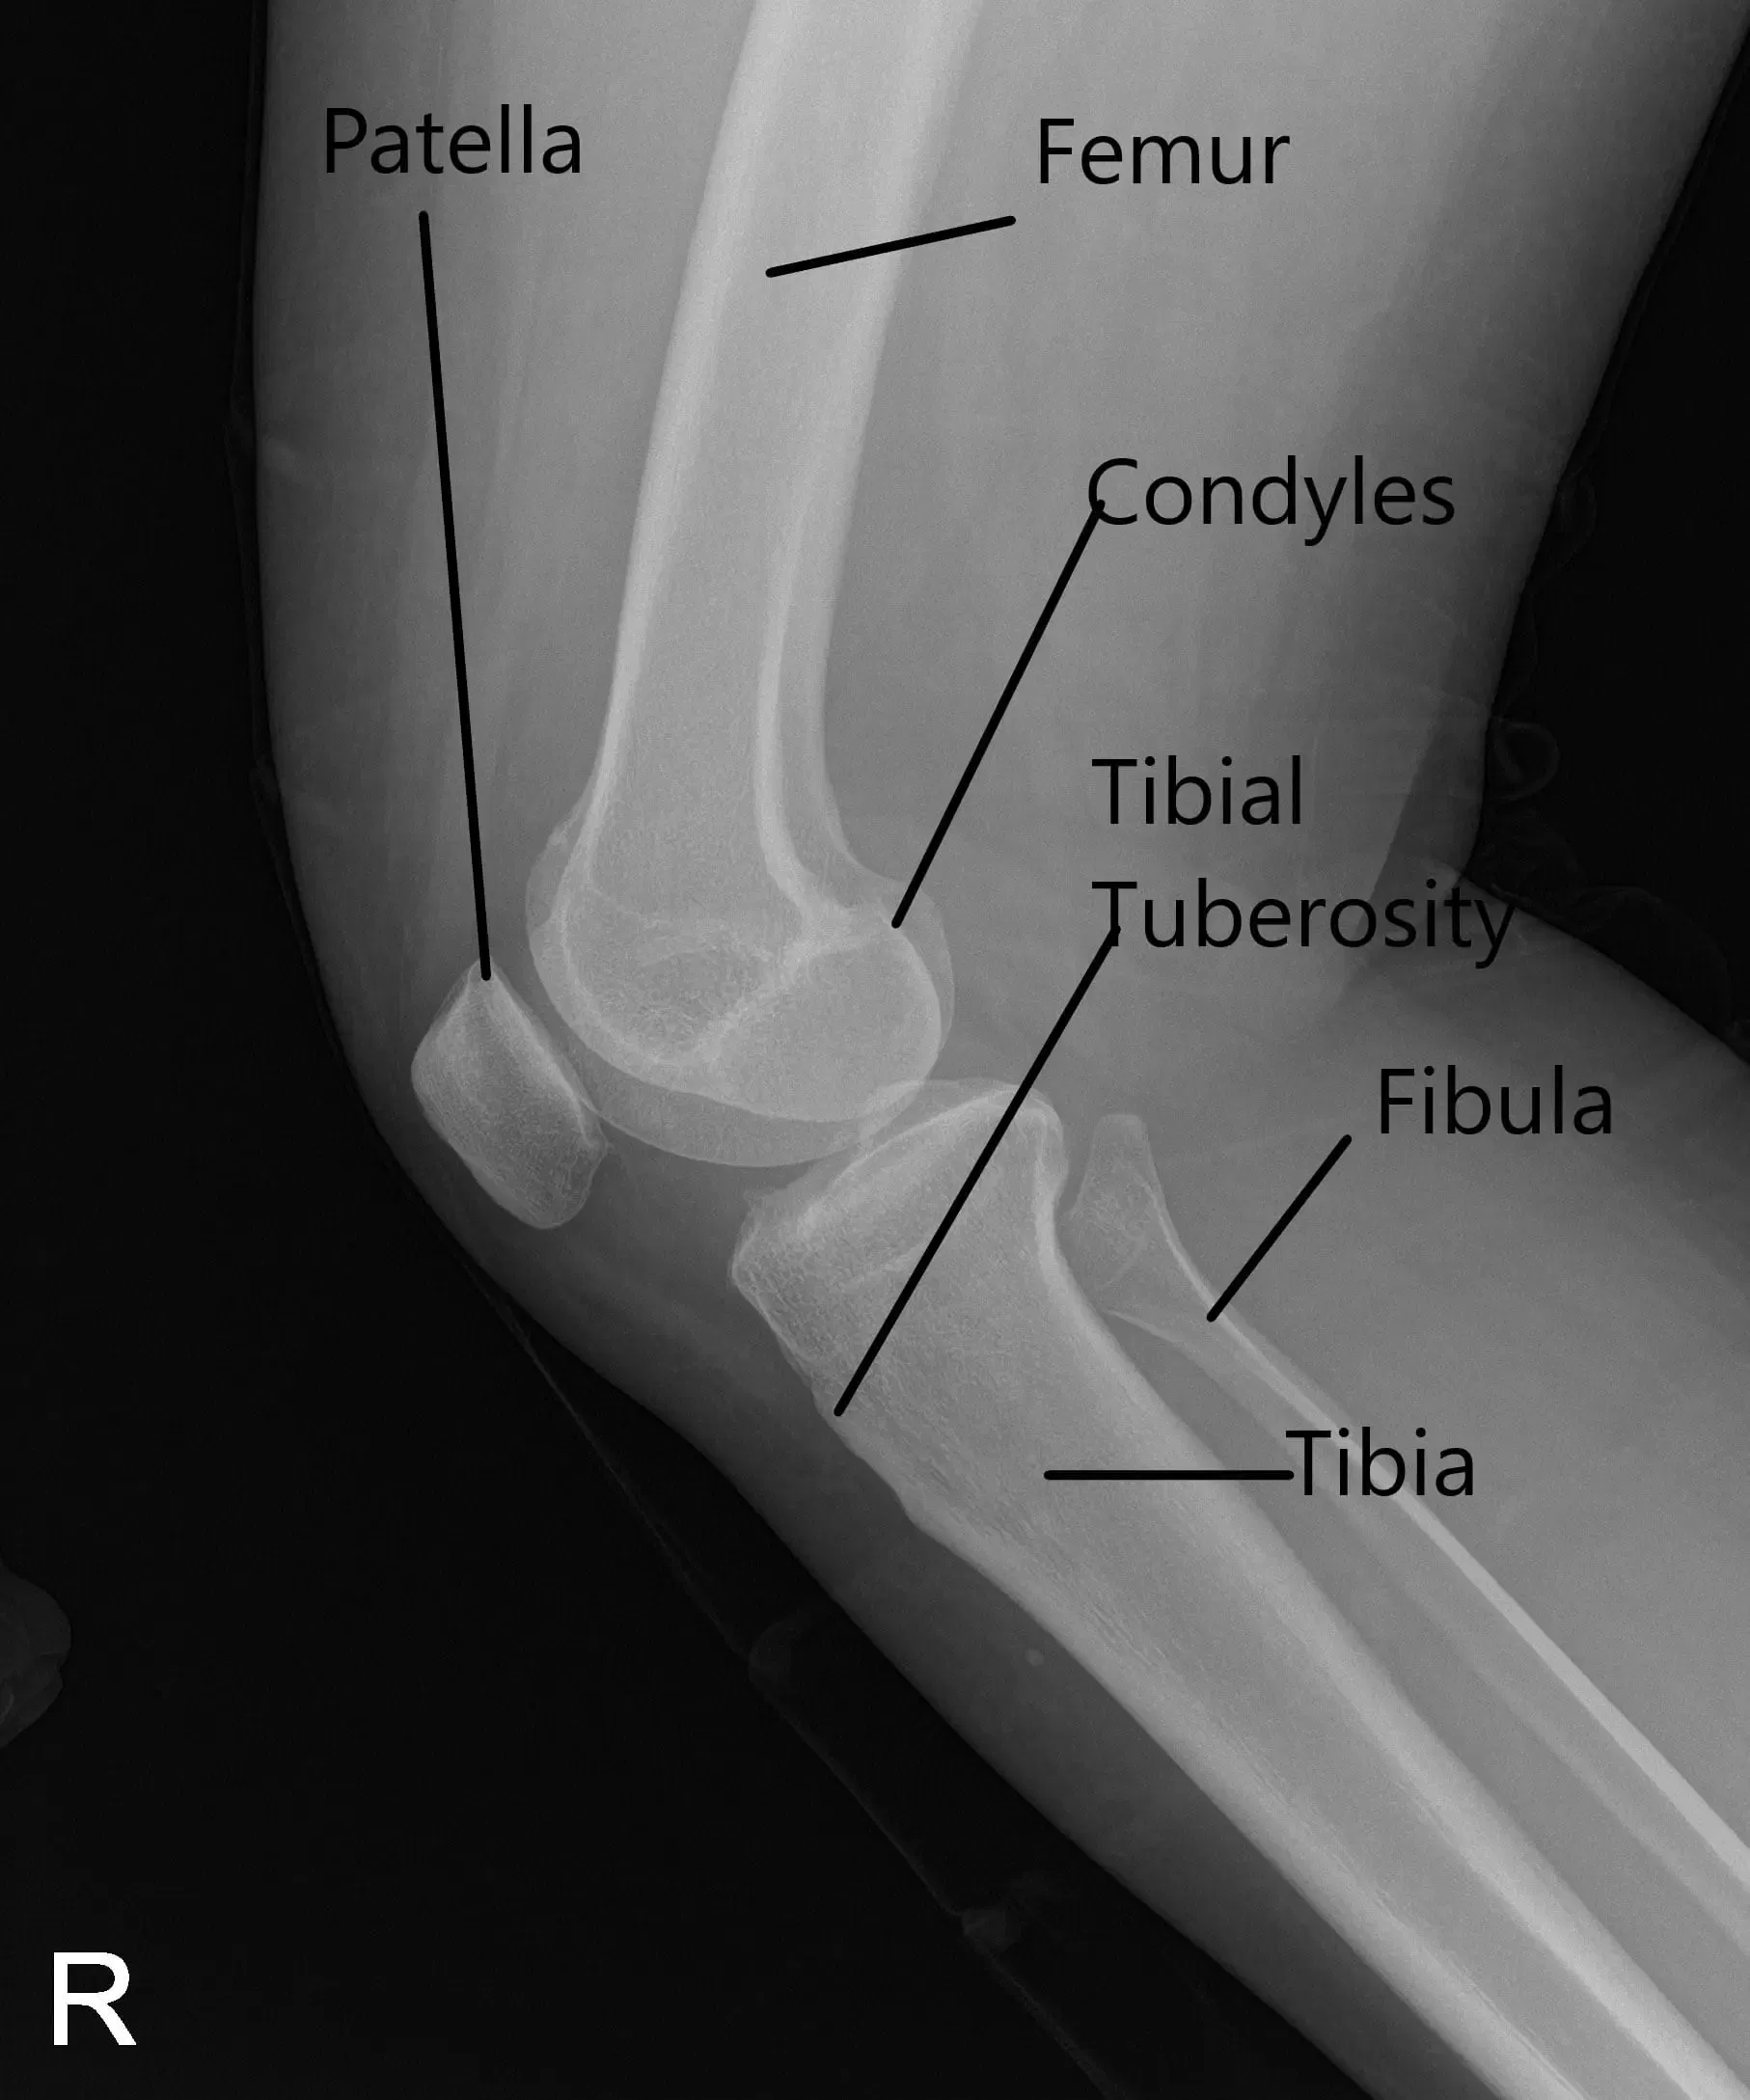

X-Ray of the right knee suggested mild osteoarthrosis in the medial and anterior compartment of the knee.